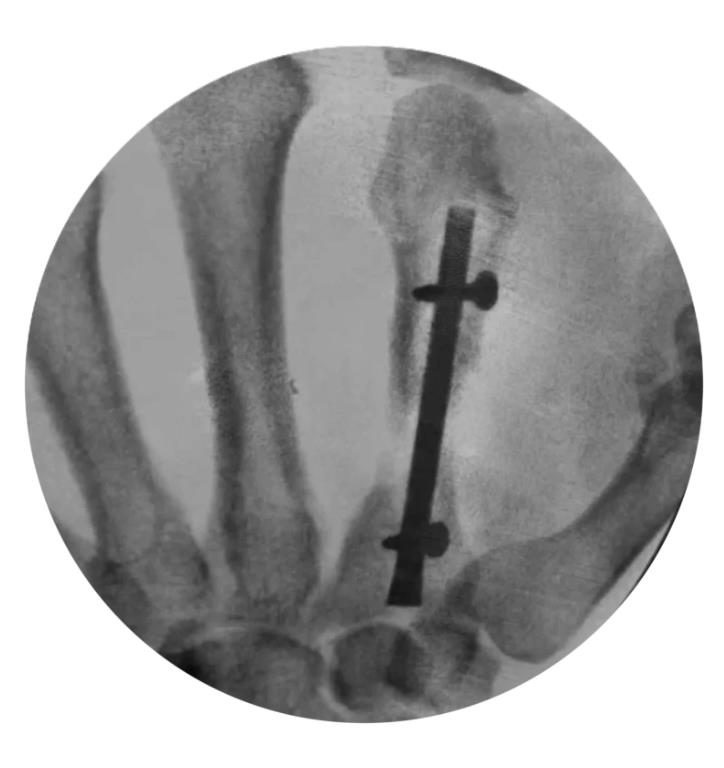

Locking Hand Nail System

• The Locking Hand Nail System from Skeletal Dynamics is an intramedullary fixation system designed for the stabilization of fractures of the metacarpals and proximal phalanges

• The device provides minimally invasive internal fixation through a headless, cannulated nail that is inserted within the medullary canal to maintain fracture alignment while minimizing soft-tissue disruption

• The system incorporates distal locking screw options to enhance rotational and axial stability, allowing controlled fixation of extra-articular fracture patterns

• Metacarpal Technique

• confirm fracture reduction and final nail position with fluoroscopy, ensuring the locking screw holes are not near fracture lines

• confirm final reduction and implant position using fluoroscopy